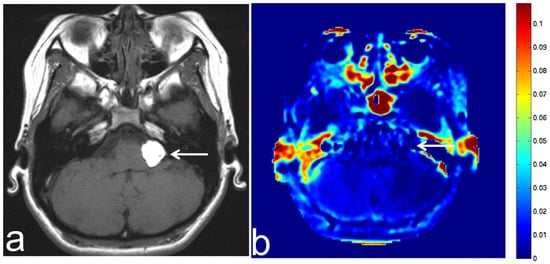

7.3. Schwannoma